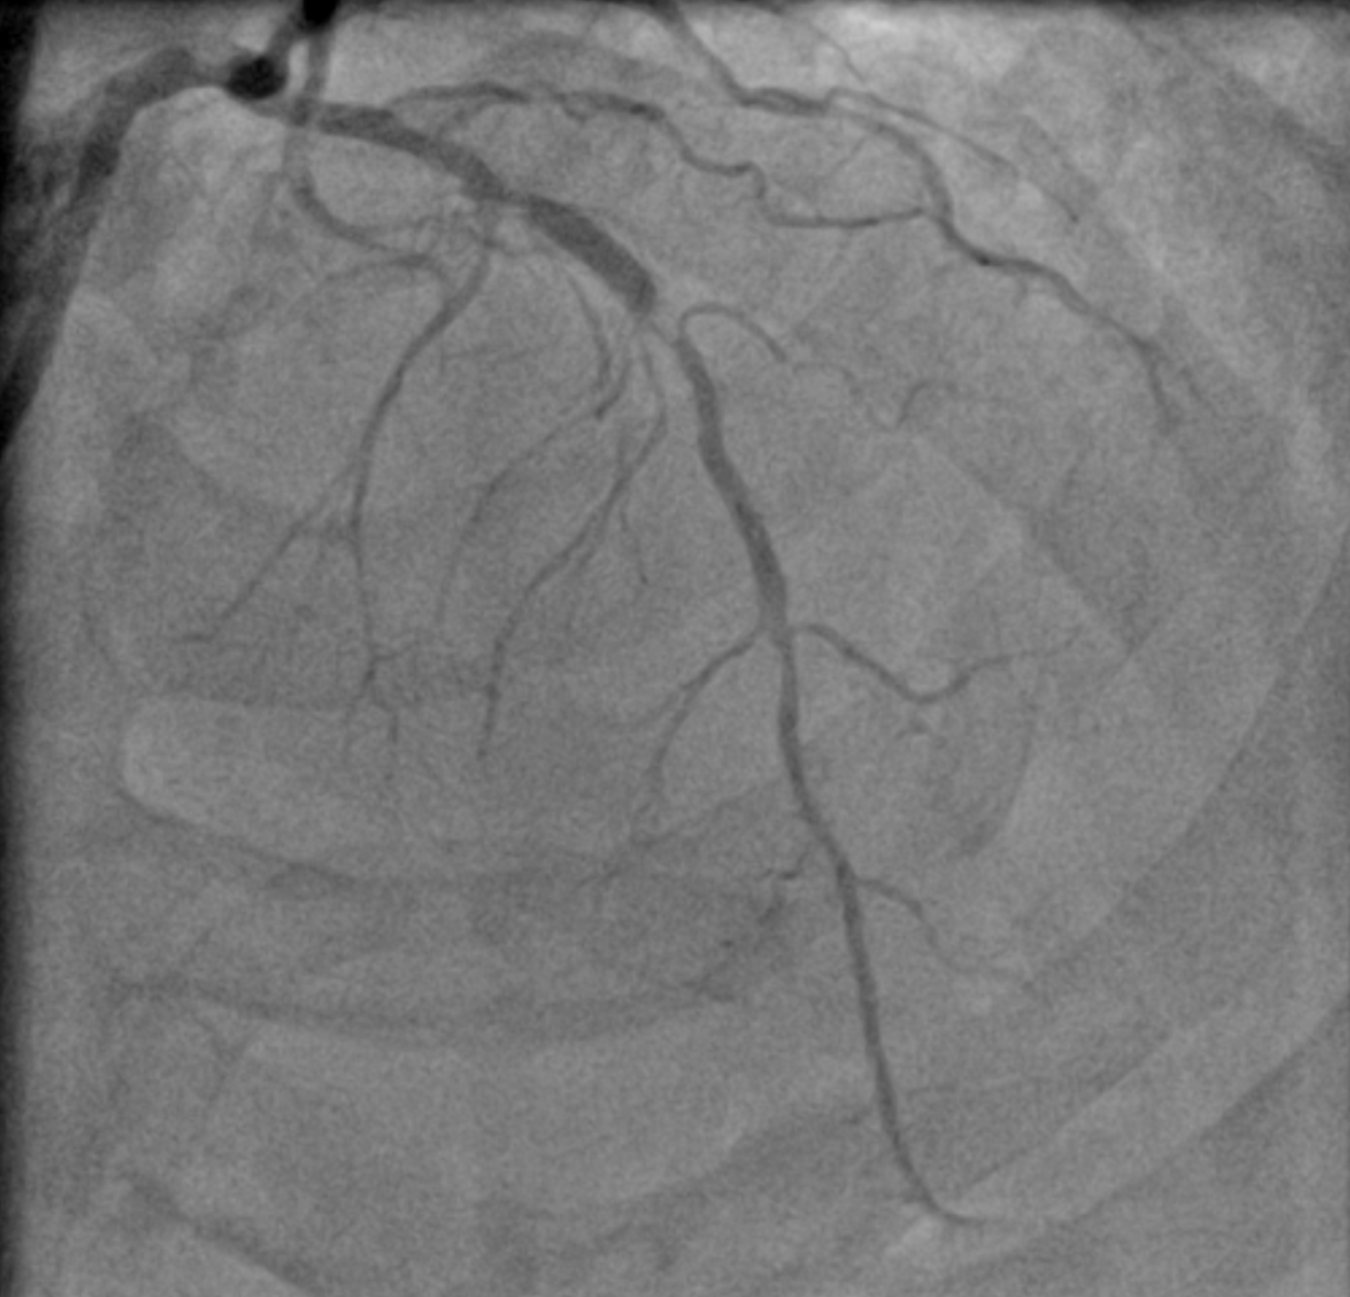

Angiography showed triple vessel disease involving LM-LAD-LCx bifurcation with eccentric calcium nodule in the ostial LCx. Severe calcification was noted throughout the proximal to mid LAD with some focal severe stenosis. RCA showed one area of severe focal stenosis.

2 ap cra.mp4